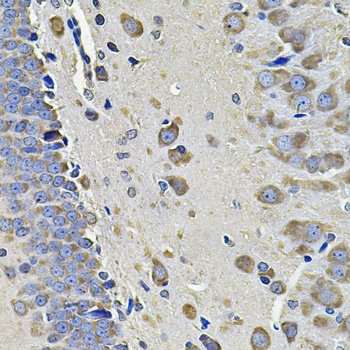

Immunohistochemistry of paraffin-embedded rat brain using EIF3C at dilution of 1:100 (40x lens).

Immunohistochemistry of paraffin-embedded mouse brain using EIF3C at dilution of 1:100 (40x lens).